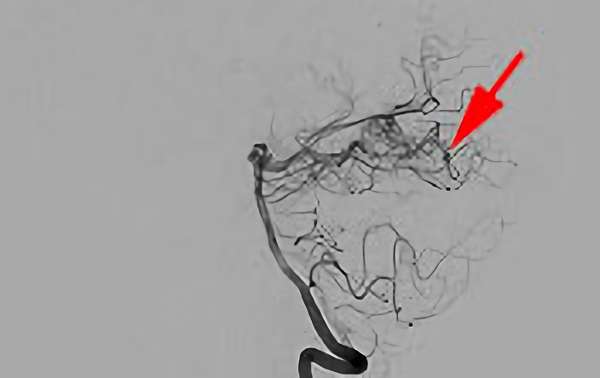

No.1576 手術前

No.1576 手術中

No.1576 手術後